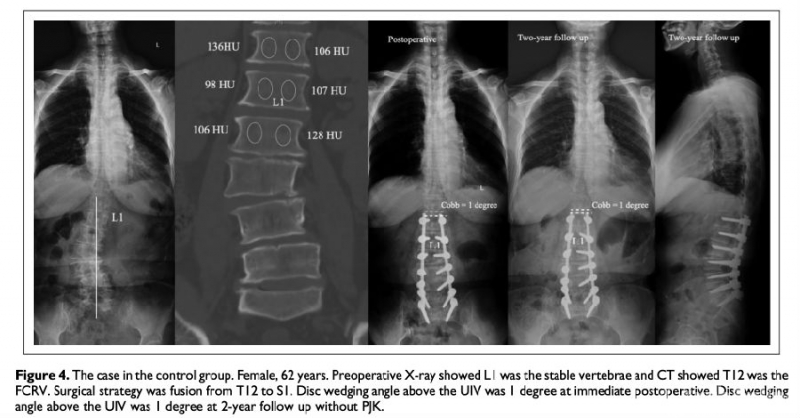

临床意义:退变性腰椎侧弯术后冠状位失衡与上端固定椎的选择密切相关。站立时间长短、透照角度对X线水平椎、稳定椎、中立椎的判断造成影响。我们提出冠状位第一反转椎(First coronal reverse vertebrae, FCRV)的概念,定义为与主弯范围内椎体凹凸侧骨密度(以CT值代表)分布相反的近端第一个椎体,FCRV与FCRV-1椎间盘剪切力大,理论上当UIV位于FCRV以下时,UIV与FCRV之间应力集中可能加速术后ASD发生。本研究目的在于分析上端固定椎位于冠状位第一反转椎以上是否可降低退变性侧弯患者术后近端邻近节段退变的风险。

材料与方法:回顾性分析116例退变性侧弯患者的临床及影像学数据,根据ASD的发生情况分为2组:研究组(ASD阳性组)和对照组(ASD阴性组)。测量腰椎椎体整体松质骨HU值和椎体凸侧和凹侧松质骨HU值。测量方法:选择椎体前皮质骨后方2mm、椎体中部、椎体后皮质骨前方2mm三个层面,上述三个层面测量值的平均值为最终椎体HU。

结果:12例患者的FCRV位于稳定椎近端第2个椎体,32例患者的FCRV位于稳定椎近端第1个椎体,35例患者的FCRV位于稳定椎,23例患者的FCRV位于稳定椎远端第1个椎体,14例患者的FCRV位于稳定椎远端第2个椎体。当UIV位于FCRV近端时,无患者出现ASD,而当UIV位于FCRV时,15.4%的患者出现ASD。在研究组中,当UIV位于FCRV时,1例患者(3.9%)出现近端侧弯进展,当UIV位于FCRV远端时,17例患者(29.8%)出现近端侧弯进展。

结论:冠状位第一反转椎远端椎间盘是冠状面应力集中点,上端固定椎位于冠状位第一反转椎之上,术后近端邻近节段退变发生率低。冠状位第一反转椎的判定比稳定椎更可靠,在上端固定椎选择上更有参考价值。

图注2:UIV位于FCRV时,术后2年近端邻近节段Cobb角无明显变化